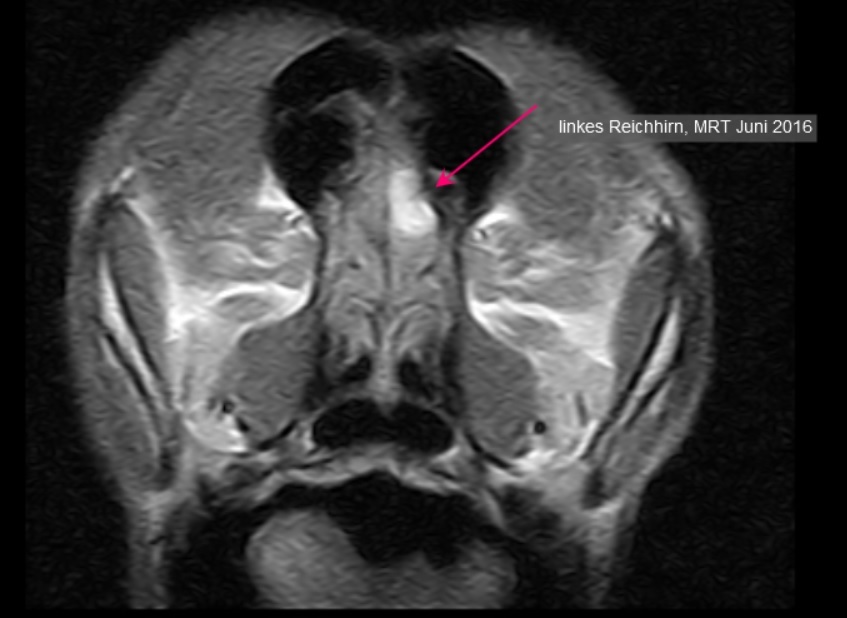

Des weiteren wurde Ghamina zu einer MRT-Untersuchung des Gehirns überwiesen. Der Befund bestätigte den Verdacht, es wurde ein flächiger Tumor im linken Riechhirn diagnostiziert. Aufgrund der typischen Kontrastmittelaufnahme bestand Verdacht auf ein Meningeom - ein Tumor, der von den Hirnhäuten ausgeht. Es zeigte sich eine mäßige Wasseransammlung (Ödem) um den Prozess. Um diese zu verringern und auch, da die Wachstumstendenz von Meningeomen positiv beeinflusst wird, erhielt Ghamina zusätzlich zum Antiepielptikum ein Kortison. Eine Operation, die aufgrund der Lokalisation und Ausdehnung schwierig gewesen wäre, kam für die Besitzerin nicht in Betracht.